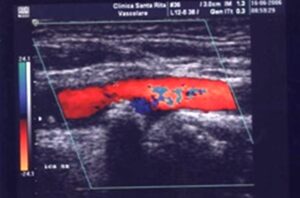

I benefici della endoarteriectomia carotidea (EA) in pazienti con stenosi sono stati dimostrati in innumerevoli trials nazionali ed internazionali. Esistono pero’ delle controversie sia sugli aspetti tecnici che sui risultati della disostruzione carotidea, ma soprattutto non esiste allo stato un sicuro monitoraggio intraoperatorio che eviti le complicanze del clampaggio carotideo. Significativa e’ la percentuale di incidenti cerebrovascolari che si verificano durante la chirurgia carotidea, fino a giungere a ictus fatale soprattutto nelle fasi di clampaggio in cui puo’ verificarsi l’insufficienza dei circoli collaterali.

Ai potenziali somatosensoriali, gia’ di utilizzo, gli esperti del Neuromed hanno aggiunto i potenziali evocati motori, in tal modo da tener sotto controllo l’integrita’ funzionale del sistema nervoso del paziente durante tutta la durata dell’intervento effettuato in anestesia generale con particolare tecnica anestetica.

Una caduta della registrazione di tale potenziale sta a significare una non corretta perfusione di alcune zone cerebrali (cui consegue il deficit) che puo’ essere evitata inserendo uno shunt temporaneo. In tal modo si puo’ effettuare un intervento di EA Carotidea anche in pazienti poco collaboranti, ansiosi e/o con deficit dell’udito e cognitivi, tranquillamente in anestesia generale.